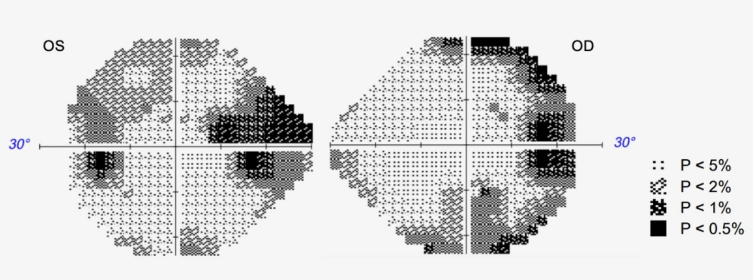

Visual field defect as the first manifestation of Alzheimer's disease.

视野缺损是阿尔茨海默病的首要表现。